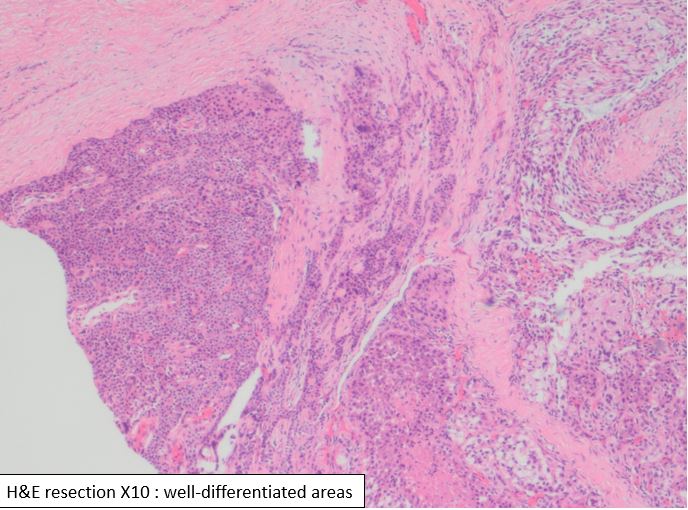

This unusual biphasic tumor has both carcinomatous and spindle cell component. The carcinomatous component is formed of granular, clear and markedly anaplastic cells. In some areas, the architecture recapitulates parathyroid differentiation: chief cells and oxyphil cells-like clusters. The areas that are poorly differentiated shows spindle and clear cell component. Keratin stain demonstrated the biphasic nature of the lesion. The tumor is positive for synaptophysin, and negative for calcitonin, Pax8, TTf-1, Sox10, and HMB45. Based on these immunostains and focal parathyroid differentiation a diagnosis of carcinoma with sarcomatoid features favoring parathyroid origin was rendered.